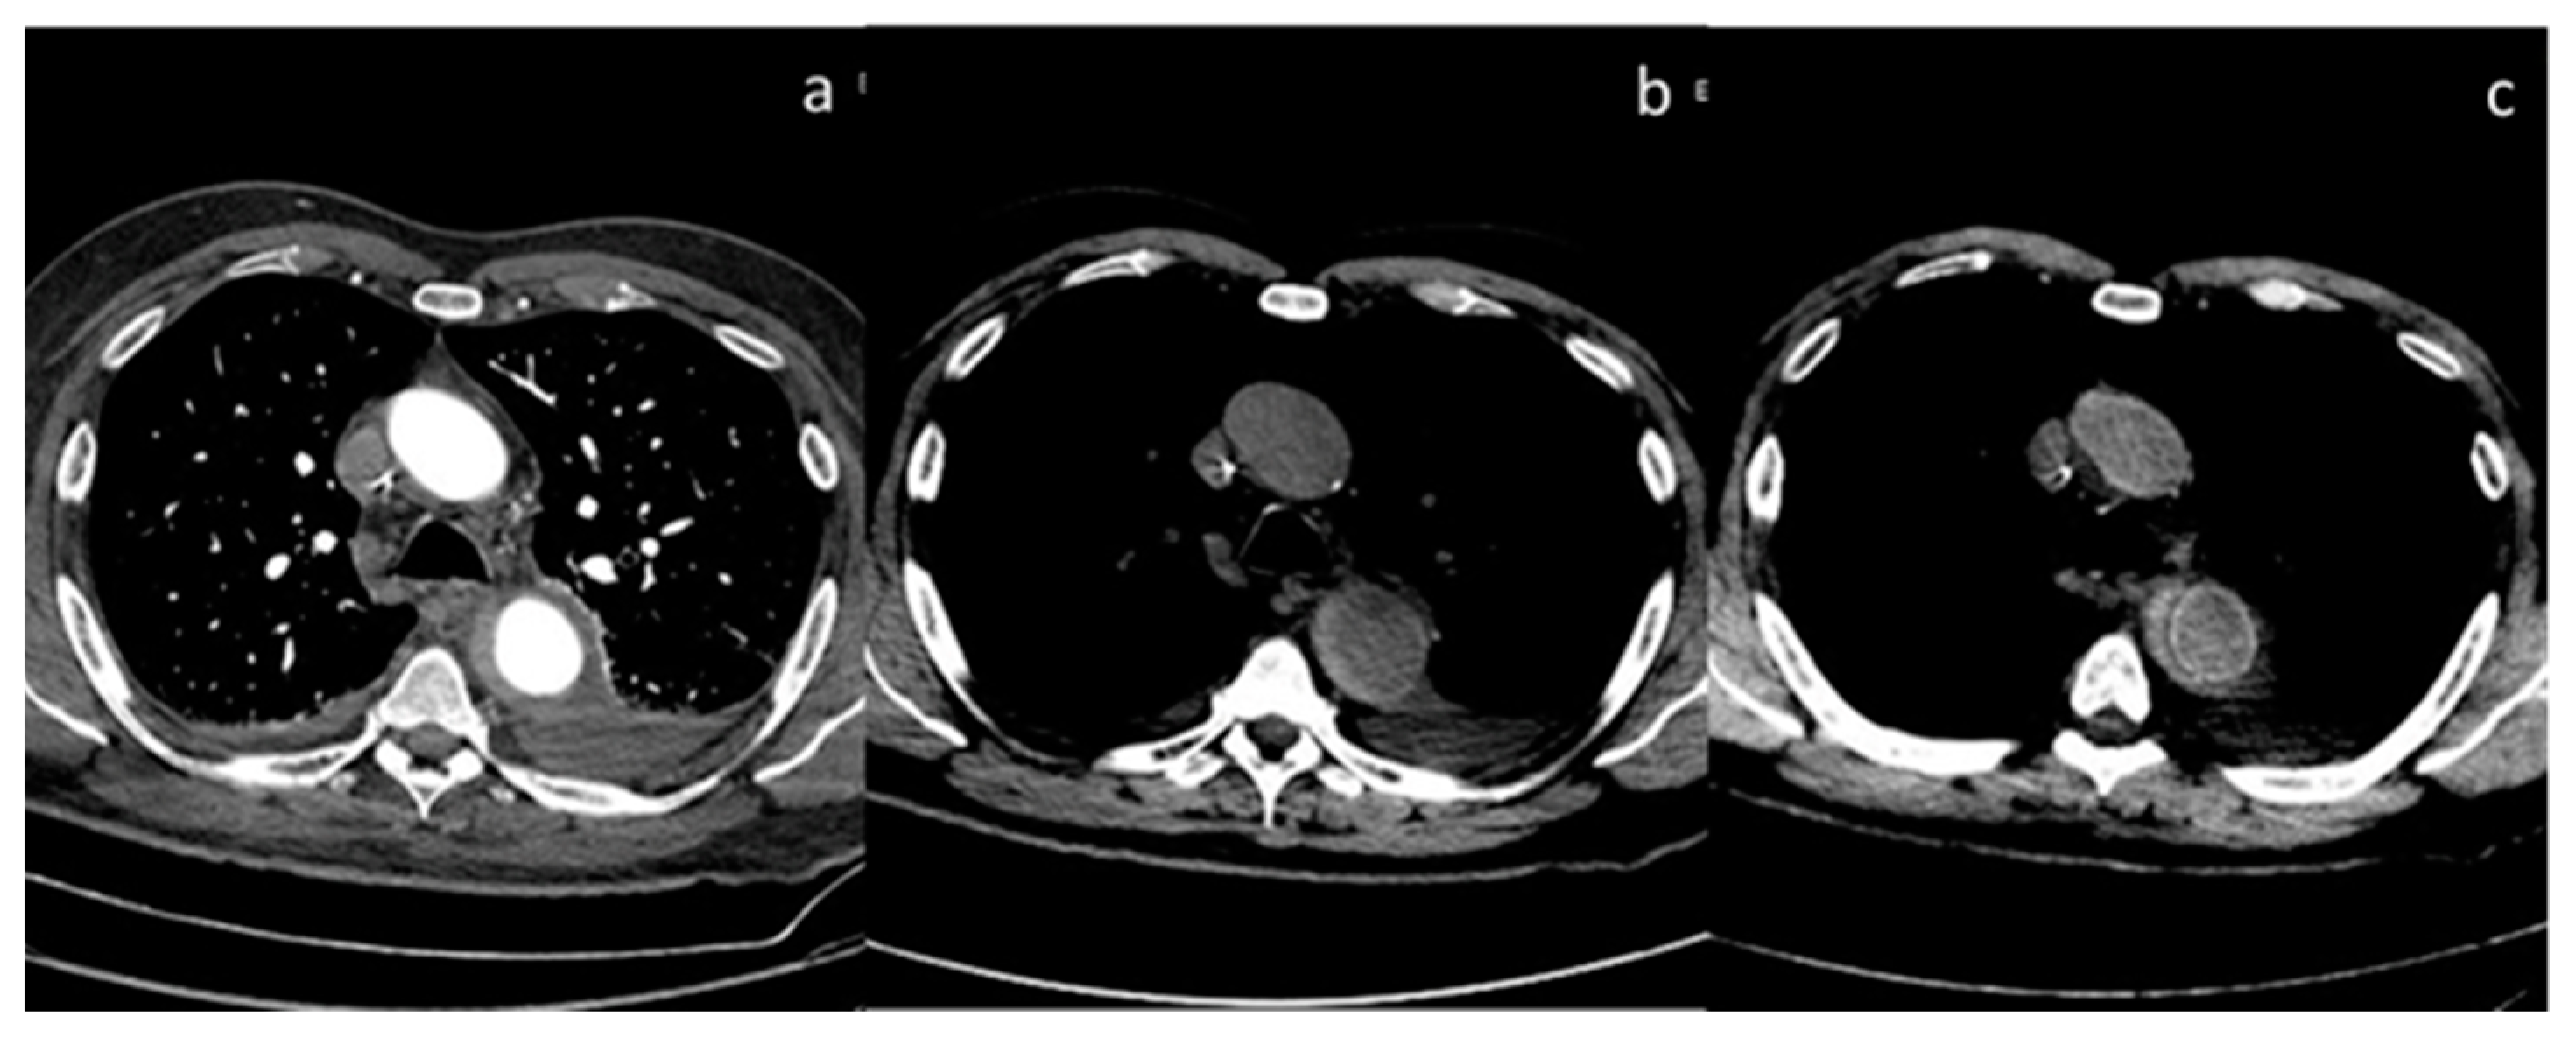

| Si-Mohamed et al. [67] Retrospective study | France | To assess whether VNC images derived from contrast dual-layer DECT images could replace TNC images for aortic intramural hematoma diagnosis in acute aortic syndrome imaging protocols by performing quantitative as well as qualitative phantom and clinical studies. | 21 | IQon, Philips Healthcare No C.I. | Dual-layer -DECT offers similar performances with VNC and TNC images for intramural hematoma diagnosis without compromise in diagnostic image quality. VNC imaging with dual-layer DECT reduces the number of acquisitions and radiation exposure in acute aortic syndrome imaging protocol. |